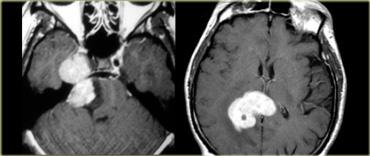

U thần kinh bao (Schwannoma) vùng góc cầu tiểu não với các đặc điểm điển hình của u ngoài trục (Chuỗi xung T2W)

Chuỗi xung T2W cho thấy một u thần kinh bao (schwannoma) nằm ở góc cầu tiểu não (CPA).

Trường hợp này minh họa rõ nét các dấu hiệu điển hình của u ngoài trục.

Có khe dịch não tủy (mũi tên vàng).

Các mạch máu dưới nhện chạy trên bề mặt não bị tổn thương đẩy lệch (mũi tên xanh lam).

Có chất xám nằm giữa tổn thương và chất trắng (mũi tên đỏ cong).

Khoang dưới nhện bị giãn rộng do sự phát triển của tổn thương ngoài trục có xu hướng đẩy lùi não.

Tất cả các dấu hiệu này cho thấy đây là một u ngoài trục điển hình.

Tại vùng góc cầu tiểu não, 90% các u ngoài trục là u thần kinh bao (schwannoma).